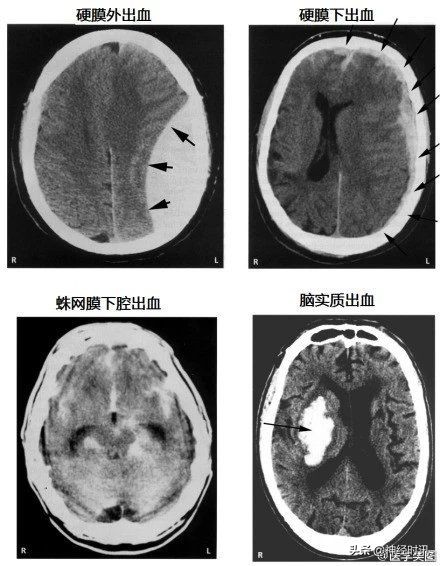

各种颅内出血

几种类型脑出血的CT表现